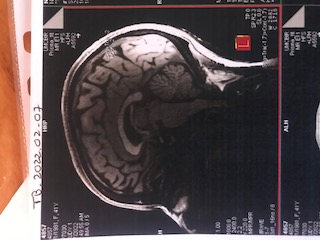

MRI testing tracks iron in the red blood cells and how it is moving through the brain. They are able to track activity in different parts of brain as the brain is busy doing tasks. Really trying to study the coordinated activity of a whole set of neural systems.